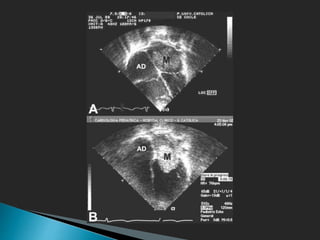

● Ecocardiografía

 TT: S 95%, TE: 99%.

 Mayor rentabilidad

 Muy sensible, poco específica

● Ecocardiografía:

• Pedunculado y móvil

• Globulares

• Superficie irregular

• Ecos heterogéneos

• Crecimiento 14 g / 1.8 cm/año